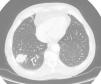

Debido a la escasa prevalencia y al bajo índice de sospecha de tal hallazgo, el diagnóstico preoperatorio no es sencillo. La tomografía computarizada mostraba un nódulo de densidad heterogénea en el lóbulo inferior derecho, que posteriormente la PAAF catalogó como adenocarcinoma metastásico de colon. Sin embargo, al revisar después las imágenes radiológicas sí se apreciaban unos bordes nodulares espiculados que dibujaban el típico signo en sol naciente, más indicativo de un proceso neoplásico primario, el cual no se identificó mediante la PAAF, así como las adenopatías halladas intraoperatoriamente (fig. 2). La rentabilidad de la PAAF para obtener el diagnóstico positivo de malignidad en nódulos periféricos de 2cm oscila entre el 80 y el 90%4. A pesar de ello, el resultado de la biopsia obtenida no fue del todo acertado. Por lo tanto, ante toda sospecha de este tipo de lesiones neoplásicas, sería conveniente tomar suficientes muestras representativas de diferentes áreas del nódulo pulmonar.